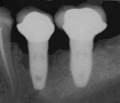

Потеря костной массы (периимплантит) на имплантатах более 7 лет у заядлого курильщика